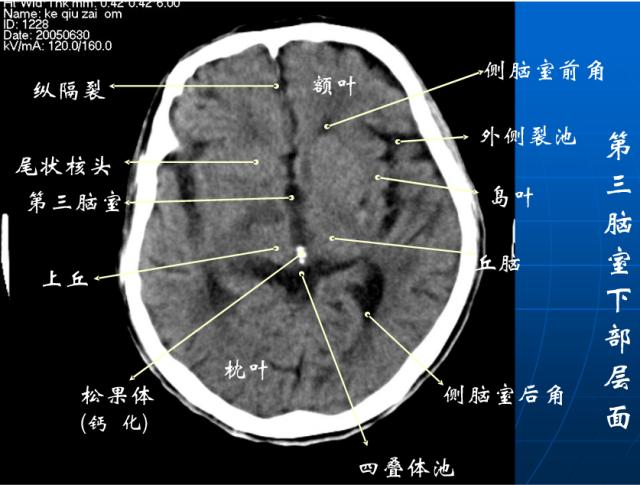

头颅ct解剖与常见出血梗死判读